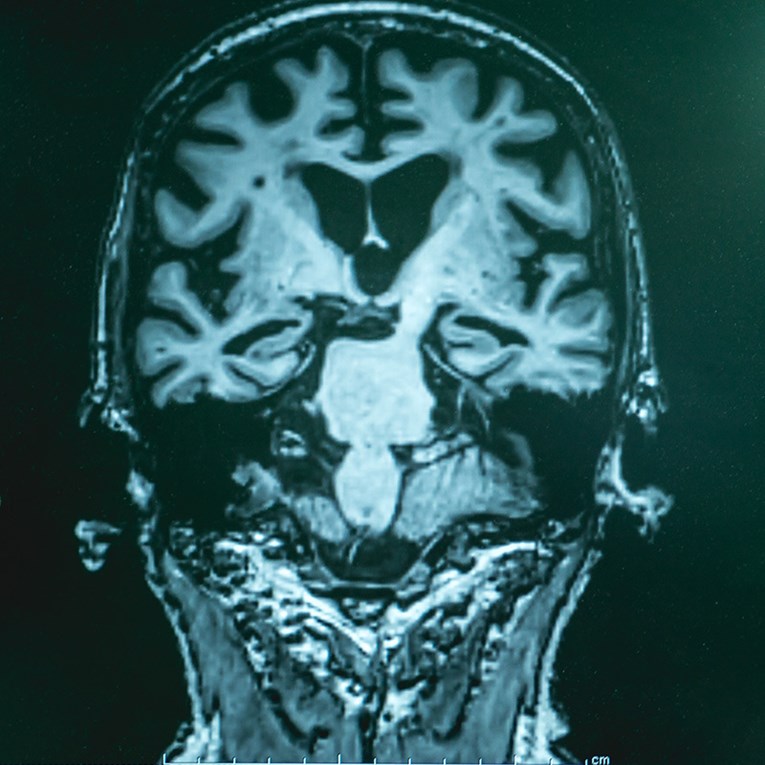

Повеќе од сто години се сметаше дека луѓето со Алцхајмерова болест не можат да се опорават од оштетувањето на мозокот што го предизвикува. Поради оваа причина, научните истражувања досега главно се занимаваа со спречување на оваа болест или нејзино забавување, а не со закрепнување.

Проучувајќи ја Алцхајмеровата болест кај глувчешки модели и во примероци од мозок од луѓе со оваа болест, тимот покажа дека еден од главните двигатели на болеста е неможноста на мозокот да одржува нормални нивоа на клучниот клеточен енергетски молекул NAD+. Покрај тоа, тие открија дека одржувањето на соодветната рамнотежа на NAD+ всушност може да го промени текот на болеста, а не само да ја спречи нејзината прогресија.

Нивото на NAD+ природно се намалува низ целото тело, вклучително и мозокот, како што старееме. Кога оваа рамнотежа е нарушена, клетките на крајот ја губат способноста да ги извршуваат клучните процеси потребни за нормално функционирање и преживување. Новата студија откри дека намалувањето на нивоата на NAD+ во мозокот на луѓето со Алцхајмерова болест е значително поизразено отколку кај здравите луѓе, а истиот модел е забележан и кај глувчешките модели.

Двете групи глувци развиле оштетување на мозокот многу слично на она што се гледа кај Алцхајмеровата болест. Бариерата што нормално го штити мозокот од штетни супстанции почнала да протекува, нервните влакна постепено се распаднале, а мозокот развил долготрајно воспаление. Во исто време, способноста за создавање нови мозочни клетки во делот од мозокот важен за меморијата била ослабена, а комуникацијата меѓу нервните клетки се влошила. Сето ова било придружено со обемно оштетување на клетките. Како резултат на овие промени, глувците имале сериозни проблеми со меморијата, учењето и ориентацијата, многу слични на оние што ги доживуваат луѓето со Алцхајмерова болест.